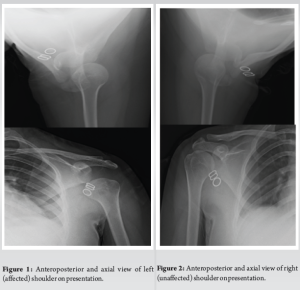

Anteroposterior (AP) radiography of the left shoulder demonstrated complete dissociation between glenoid and humeral head (Fig. 1). This led to a growing suspicion of the patient being a habitual shoulder dislocater. Owing to the limited abduction of the shoulder, a Velpau axillary view was carried out. The AP positioning of the humeral head was perceived to be within normal limits (Fig. 1). Opposite side radiographs were normal (Fig. 2).